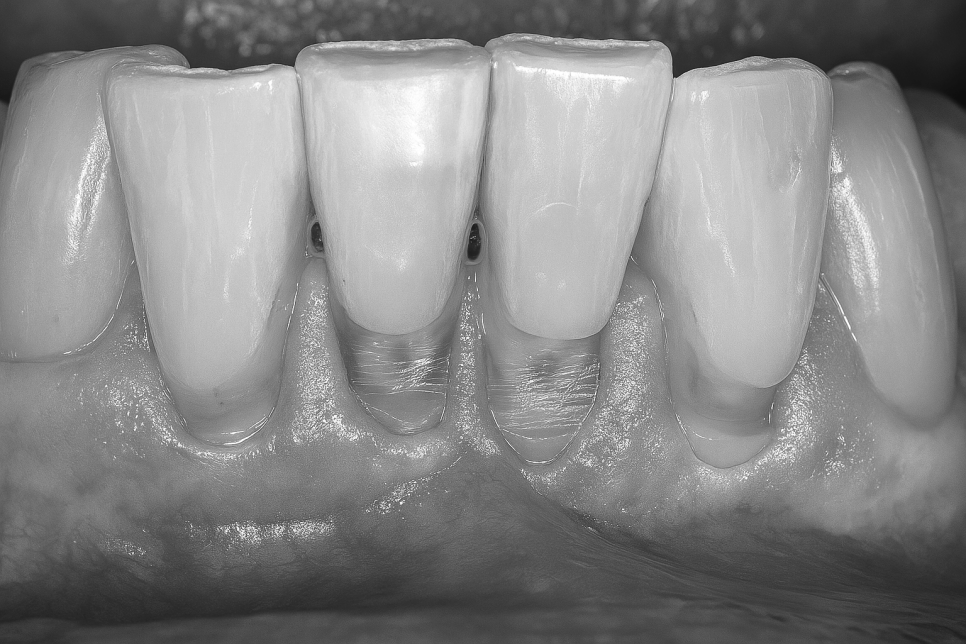

치아는 구조적으로 잇몸 밖으로 나온 부분과

안쪽에 있는 부분으로 나뉩니다.

그리고 이 둘이 만나는 지점을

치아 경부라 합니다.

그리고 이 지점의 법랑질의 소실이 일어나는

비우식성 병변을 치경부마모증(Cervical Abrasion)

이라 부릅니다.

이곳은 법랑질층이 얇고 가려져 있어서

외부 자극에 취약한 편이랍니다.

초기 소실 시점에는 그 증세가 미미한 편이나

법랑질층이 점차 닳아 없어지고 상아질이

드러나게 되면서 여러 불편감을 줄 수 있는데,

이때 시린 이 증세가 나타나게 됩니다.

패인 자국은 V자 혹은 U자 형의

모양을 띠는 편이며, 언뜻 보면 이가

길어보이는 착각을 일으키기도 합니다.